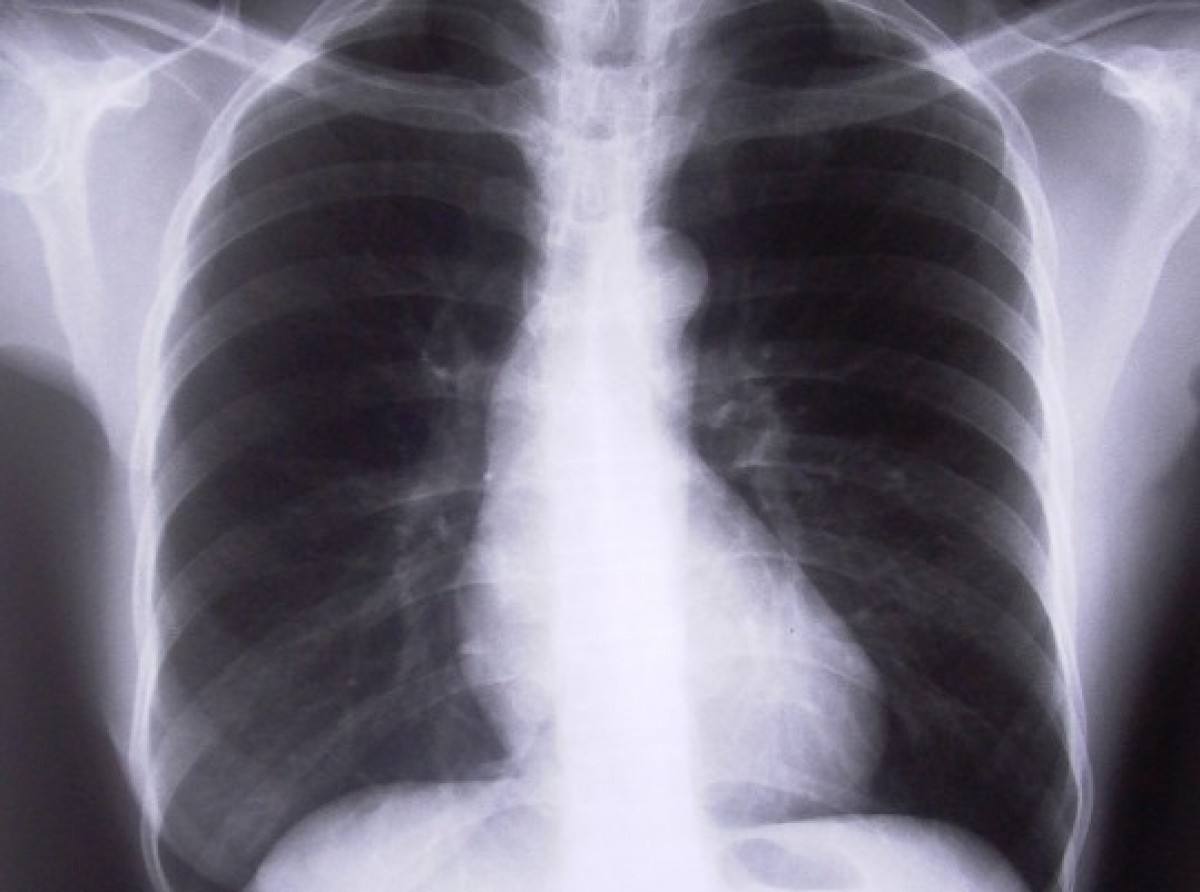

Taču plaušu digitālā rentgenogrāfija janvārī darbu vēl turpinās vecajā ēkā Saules ielā 31, pirmdienās un trešdienās no pulksten. 8.30 līdz 12.30.